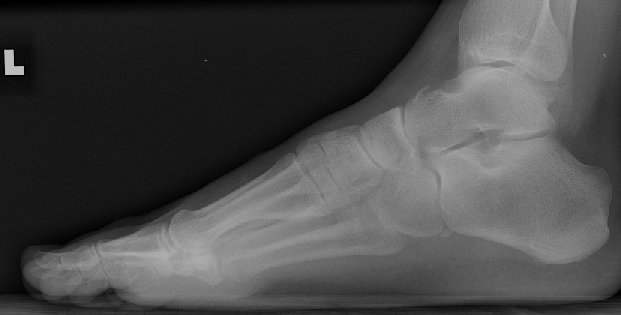

Return to Talus Fracture (Avulsion)